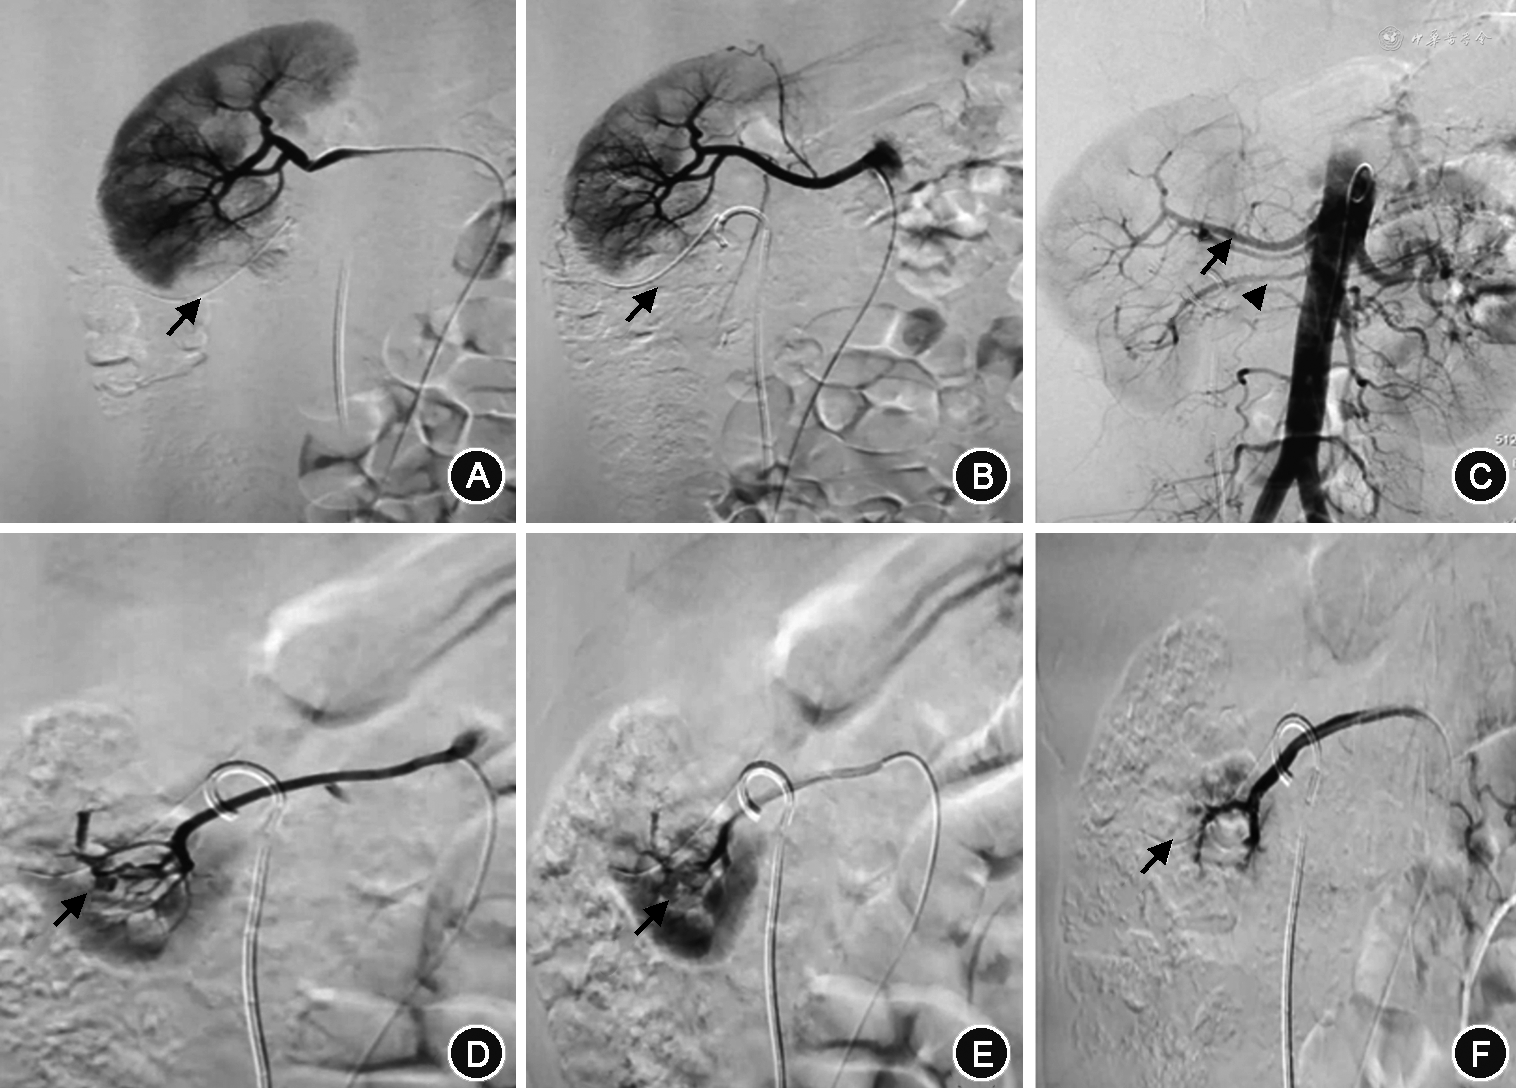

2. 诊断与治疗方法:27例患者均在保守治疗无效后急诊局麻下经皮股动脉穿刺插管至患肾动脉,行选择性肾动脉造影,初次造影结果为阴性,未发现出血部位。再保守治疗1~3 d无效后,经反复肾动脉造影,最后均发现血管损伤病变。其中15例假性动脉瘤(图1A),4例动静脉瘘(图1B),8例假性动脉瘤合并动静脉瘘(图1C)。23例行2次、4例行3次肾动脉造影。分析原因,其中一味追求选择性肾动脉造影,遗漏副肾动脉供血所致出血5例12次(图2、3);两处以上出血,只处理一处出血3例6次;初次未发现出血病变,第二次才发现者17例36次;选择栓塞物不当2例4次。诊断明确后同时行超选择栓塞术,栓塞当时即复查肾动脉造影,27例显示病变完全栓塞,出血点消失,术后患者严重血尿症状立即得到改善,1周内肉眼血尿及腰部不适症状全部消失,尿色转清,血红蛋白持续稳定,拔出肾造瘘管后患者出院;其中5例出现栓塞后综合征,表现为低热、腰部胀痛不适等症状,给予退热、止痛等对症处理后症状消失。